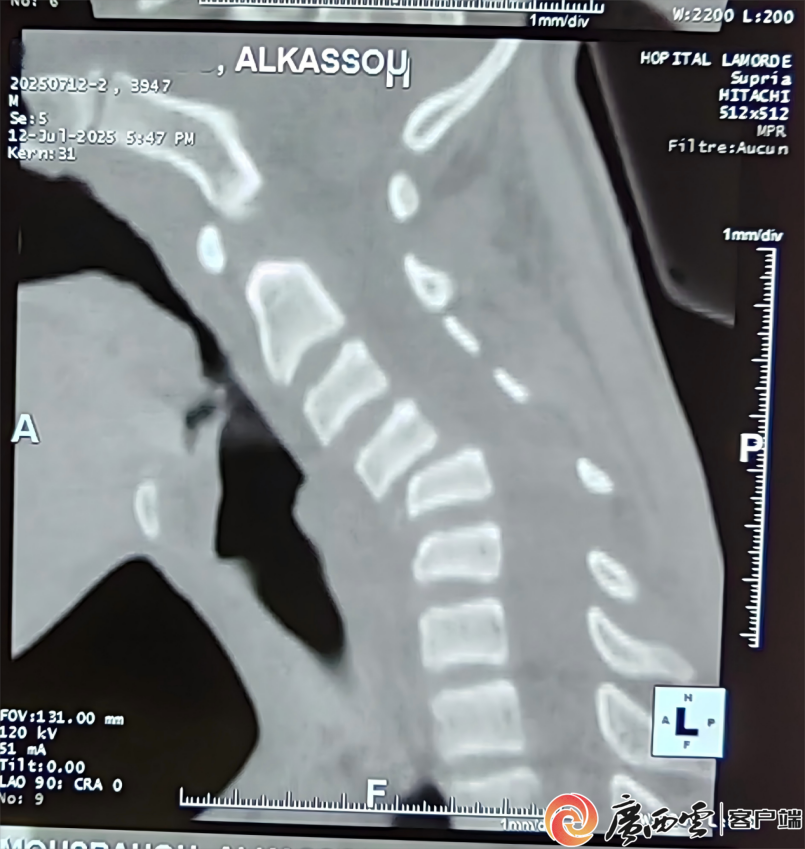

术前影像学显示颈4-5骨折、脱位并关节突交锁。援尼日尔中国医疗队供图 面对挑战,中国医疗队与尼日尔综合医院当地同仁经过周密论证,最终决定迎难而上。医疗团队制定详细预案,为患者实施“颈椎前路复位、植骨融合及钉板系统内固定术”。手术由中国医疗队副主任医师李小峰主刀,在麻醉团队严密监护下,以精细的手法撬动交错的关节,于狭窄的椎间隙精准植入骨块,并在颈椎前方安装钉板固定系统。手术全程如履薄冰,最终成功复位并稳定了损伤节段。 术后第3天,该少年已能在走廊练习行走。当看到中国医生李小峰时,少年停下脚步,努力挺直脊背,缓缓而坚定地竖起大拇指。这一无声的感激跨越了语言障碍,温暖了在场所有人。术后一周,患者恢复趋势良好,可稳健行走,右手已能抓握钥匙,腕肘关节活动自如,虽然右臂力量尚未完全恢复,无法上举,但希望的曙光已清晰可见。